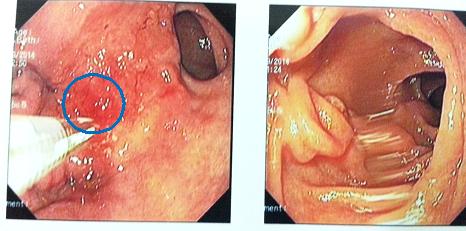

Nội soi dạ dày:

Hình 2: Mặt trước hang vị dạ dày có tổn thương gồ ghề đường kính 2cm (vòng tròn xanh) Đã được sinh thiết làm xét nghiệm mô bệnh học (giải phẫu bệnh)

Kết quả giải phẫu bệnh: Ung thư biểu mô tuyến kém biệt hóa. Xét nghiệm Her-2/neu âm tính.